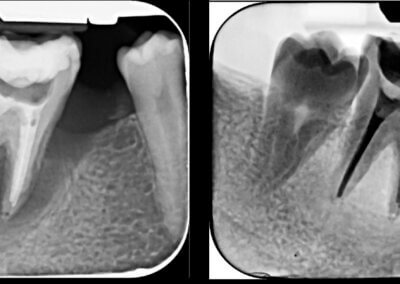

Utilizarea tehnicilor moderne asigură un tratament rapid, precis și confortabil pentru pacient.